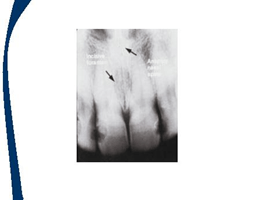

En las imagenes aparecen flechas que representan la localización de los landmarks o puntos de referencia

Espina nasal anterior

Fosas nasales

Sutura palatina media

Agujero nasopalatino